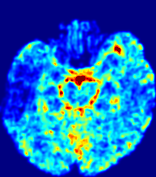

4.3.1 Advection Imaging via Advection-Diffusion

Slice #1Slice #2Slice #3Slice #4Slice #5Slice #6𝐕gt𝟐subscriptnormsuperscript𝐕gt2\|\bf{V}^{\text{gt}}\|_{2}Refer to captionRefer to captionRefer to captionRefer to captionRefer to captionRefer to caption𝐕est𝟐subscriptnormsuperscript𝐕est2\|\bf{V}^{\text{est}}\|_{2}Refer to captionRefer to captionRefer to captionRefer to captionRefer to captionRefer to captionRefer to caption1.51.51.51.21.21.20.90.90.90.60.60.60.30.30.30.00.00.0(mm/s)𝑚𝑚𝑠(mm/s)Destsuperscript𝐷estD^{\text{est}}Refer to captionRefer to captionRefer to captionRefer to captionRefer to captionRefer to captionRefer to caption0.0150.0150.0150.0120.0120.0120.0090.0090.0090.0060.0060.0060.0030.0030.0030.0000.0000.000(mm2/s)𝑚superscript𝑚2𝑠(mm^{2}/s)

Figure 14: PIANO identifiability testing: advection imaging via advection-diffusion. Top row shows 𝐕gt2subscriptnormsuperscript𝐕gt2\|{\bf{V}}^{\text{gt}}\|_{2} used for simulating ground truth pure advection. Rows below show the estimated 𝐕est2subscriptnormsuperscript𝐕est2\|{\bf{V}}^{\text{est}}\|_{2} and Destsuperscript𝐷estD^{\text{est}} on corresponding slices. Note that the plotted value scale for Destsuperscript𝐷estD^{\text{est}} is 0.01 of that for 𝐕gt2subscriptnormsuperscript𝐕gt2\|{\bf{V}}^{\text{gt}}\|_{2} and 𝐕est2subscriptnormsuperscript𝐕est2\|{\bf{V}}^{\text{est}}\|_{2}.

We use the same ‘Advection Imaging’ simulation of Sec. 4.2.1 as the concentration dataset for PIANO. However, instead of modeling pure advection (Eq. 15), we let PIANO estimate both velocity 𝐕estsuperscript𝐕est{\bf{V}}^{\text{est}} and diffusivity Destsuperscript𝐷estD^{\text{est}} via the advection-diffusion PDE (Eq. 2) underlying the proposed PIANO model. Fig. 14 shows the estimated 𝐕est2,subscriptnormsuperscript𝐕est2\|{\bf{V}}^{\text{est}}\|_{2}, and Destsuperscript𝐷estD^{\text{est}} fields for one patient. Although PIANO has the freedom to estimate both a velocity and a diffusivity field from pure advection, PIANO differentiates well between advection and diffusion: the estimated 𝐕est2subscriptnormsuperscript𝐕est2\|{\bf{V}}^{\text{est}}\|_{2} successfully reproduces the ground truth 𝐕gt2subscriptnormsuperscript𝐕gt2\|{\bf{V}}^{\text{gt}}\|_{2} governing the simulated advection process, just as it already did in the ‘Advection Imaging via Advection’ test (Fig. 12). More importantly, the estimated diffusivity Destsuperscript𝐷estD^{\text{est}} is orders of magnitudes smaller than 𝐕est2subscriptnormsuperscript𝐕est2\|{\bf{V}}^{\text{est}}\|_{2}, indicating the estimated diffusion is negligible compared to the estimated advection, which is highly consistent with the underlying pure advection of the simulated data.